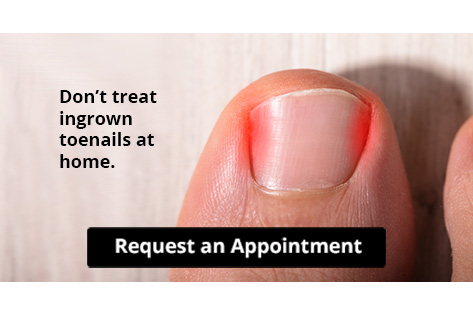

Let the Expert Treat Your Ingrown Toenails

Some of the most common foot problems seniors are susceptible to include foot ulcers, ingrown toenails, fallen arches, and fungal nails. A foot ulcer is an open sore on the foot and can be a result of diabetes and decreased sensation in the feet. An ingrown toenail is defined as when the nail grows into the side of the toe. Fallen arches are indicated by the instep of the foot collapsing. A fungal nails is a condition that results in deformed and discolored toenails.